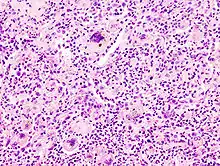

Melanom-Metastase im Lymphknoten.

• Tumoren:

• Naevuszellnaevus

• Malignes Melanom